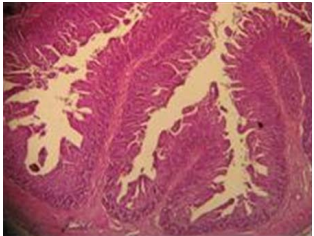

Figura 1: Microfotografía de yeyuno correspondiente a los animales testigos y tratados con el prebiótico

Foto de yeyuno pertenecientes a los animales con prebiótico (extracto de alcachofa – Bedgen 40)

6. El estudio histológico no permitió determinar el cálculo de la superficie de absorción debido a que en el grupo prebiótico las válvulas de Kerkring aparecieron muy voluminosas y plegadas haciendo imposible la medición de las vellosidades. No obstante, el corte histológico evidencia cualitativamente, abundante cantidad de vellosidades.